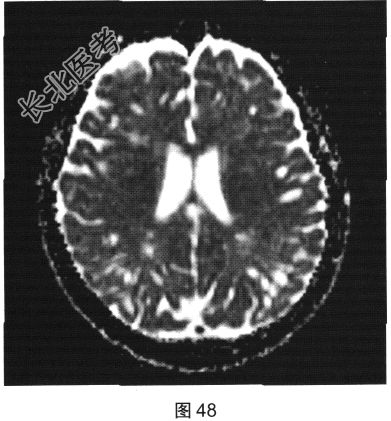

- 多项选择题2.[提示]患者行FLAIR、DWI及增强扫描,见图45~图54。该患者MRI影像的主要阳性表现有( )

C、双侧放射冠及半卵圆中心多发条状、圆形及卵圆形异常信号灶

E、病灶呈长T1、长T2信号,FLAIR为低信号,DWI为低信号,ADC为高信号